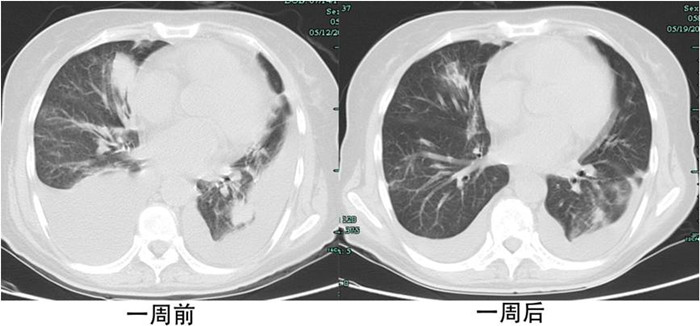

用藥一天后,劉女士咳嗽及胸悶癥狀得到了緩解,一周后,咳嗽及胸悶完全消失,兩周后雙肺的轉(zhuǎn)移病灶及癌性淋巴管炎也明顯減輕,甚至雙側(cè)胸腔積液也明顯減少。